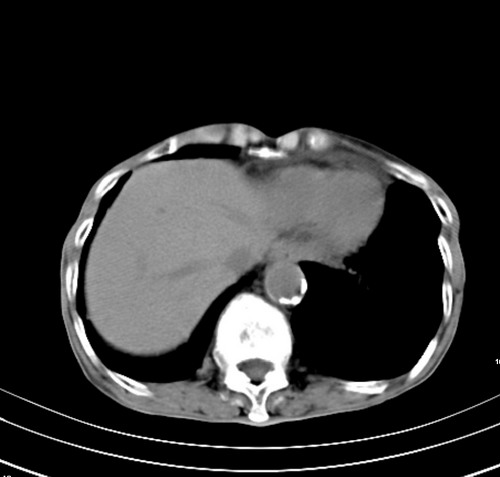

病人,女,79岁,主要因腹疼二月入院,彩超,肝,胆,脾,未见异常,胸透上消化道造影未见异常,化验白细胞增高,内科医生让做胸部ct检查,因为熟人多做了腹部(外科会诊考虑胆囊炎).现ct片如下请假各位战友.

1 气管旁、隆突下淋巴结明显肿大,肝左叶外侧段低密影,都考虑转移。

2 肝右后叶下段明显增大,片状低密影,但因各种伪影显示不佳,不排除病变。

后中纵隔团块影,伴气管、食道受压移位,首先考虑转移瘤,肝s5段低密度灶。建议增强检查,另外其结肠是否有问题请提供,右肺部分肺叶局限含气增多,考虑局限肺气肿。

后中纵隔团块影,伴气管、食道受压移位,首先考虑转移瘤,肝表现同11773。